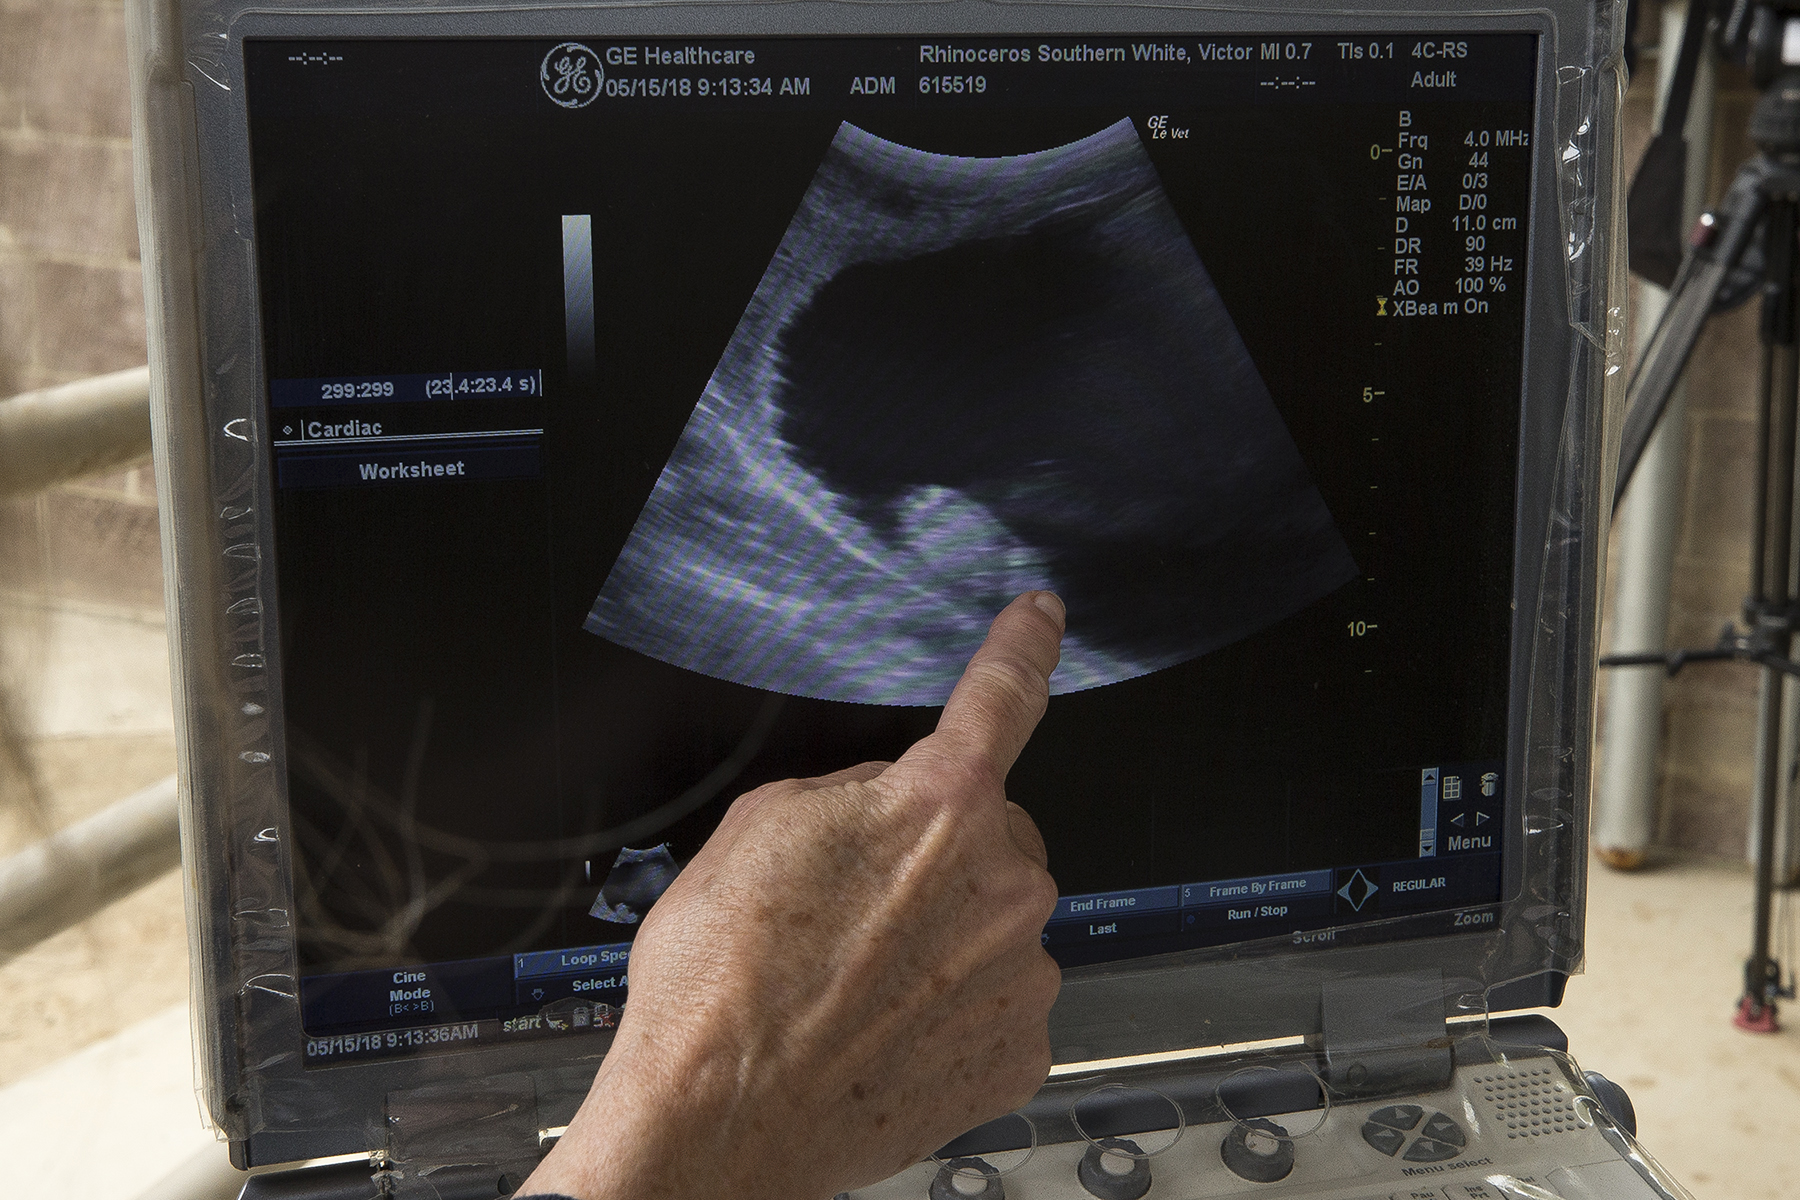

A southern white rhino is pregnant with a lot of help from science.

Researchers at the San Diego Zoo Institute for Conservation Research announced yesterday the artificial insemination of rhino named Victoria with sperm from a male southern white rhino could be first step in helping its northern white rhino cousins face down extinction.

“Just the fact that we have been able to confirm this pregnancy while the embryo is just a few weeks old is tremendously important and is all due to the work that animal care staff have put into developing relationships with these rhinos,” Parker Pennington, post doctoral associate, said in a statement.

And Victoria is cooperating in the ultrasounds and with researchers who are caring for her.